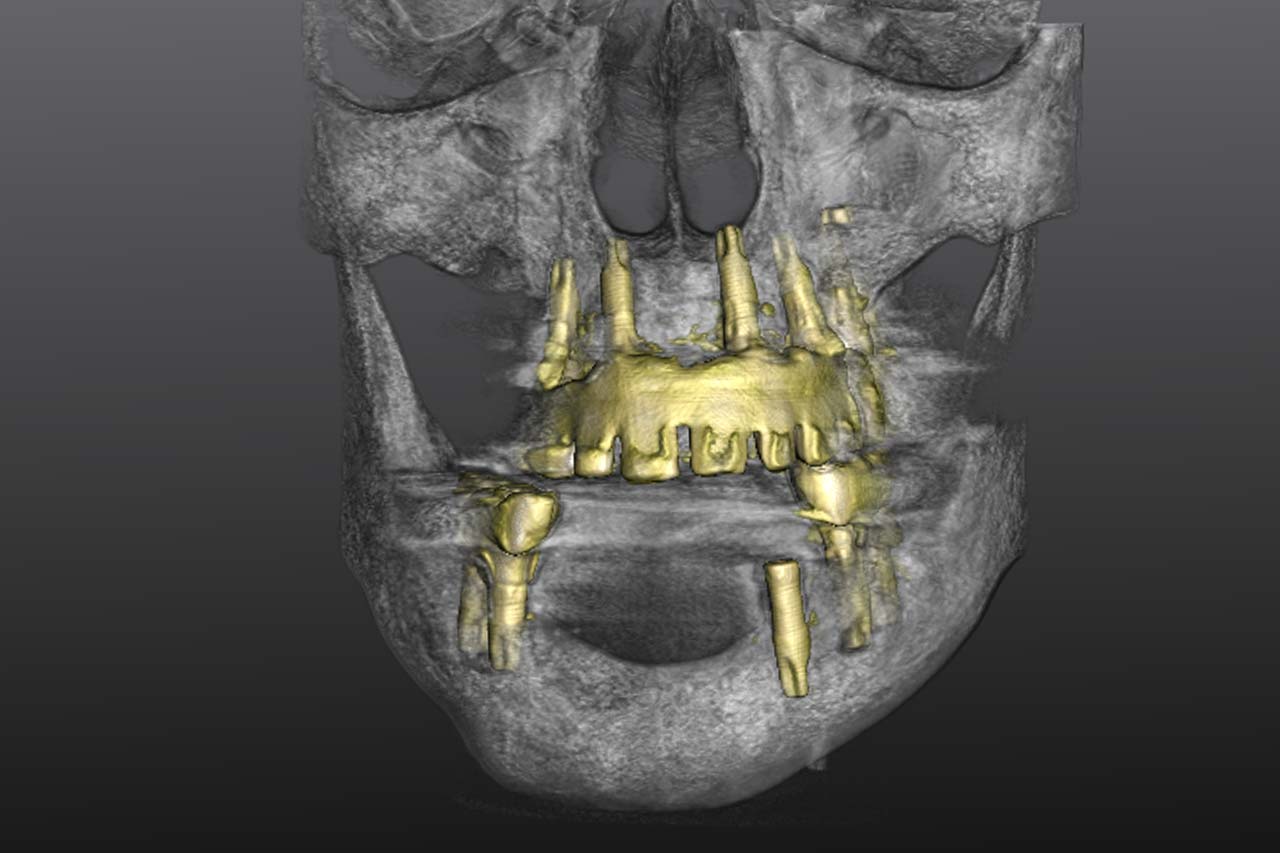

Nutzen des digitalen Workflows bei der prothetischen Rekonstruktion kompromittierter und gesunder Patienten

Prof. Dr. Dr. Walter Lückerath, Bonn

„Implantat-Chirurgie kompromittierter Patienten und was können wir für Gesunde daraus lernen?

OÄ Dr. Marie-Sophie Katz, Aachen